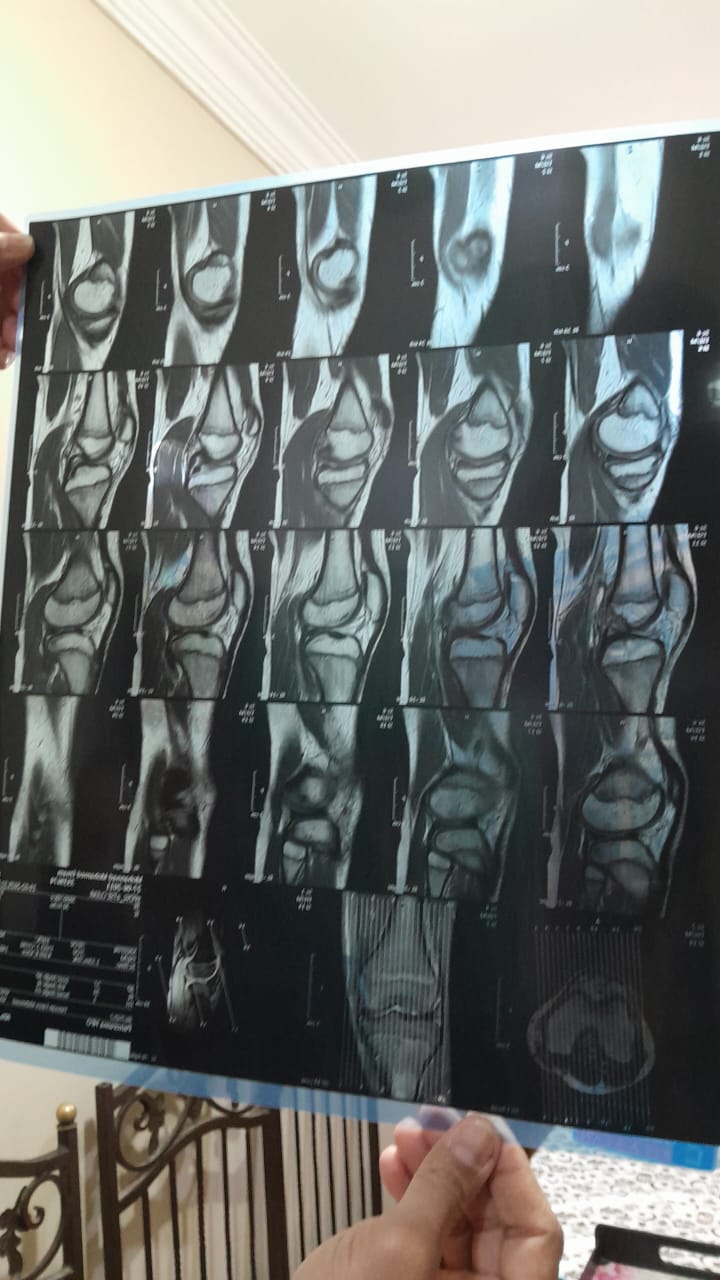

وأضاف والد الطفل مهند،م: اللي حصل إننا بقالنا 3 شهور تقريبا ابني عنده قطع في غضروف الركبة ورباط صليبي، وروحت لدكاترة كتير عشان أشخص الحالة وأنفقت أموالا طائلة، واستقريت على طبيب شهير (إبراهيم، ج) لعمل الجراحة وهو طبيب مشهود له بالكفاءة في التخصص، ولكنه يجري الجراحات في مستشفيات معينة ومحددة، منها مستشفى ABC، وبالفعل عند تقديم طلب لإدارة التعاقدات بمقر عملي بالمصرية للاتصالات تعاونت الإدارة على الفور وأنهت جميع الإجراءات سريعًا وراسلت إدارة مستشفى ABC موضحة أنها متحملة كافة النفقات، وحدد الطبيب موعدا للجراحة أمس، وجاء بالفعل بعد تجهيز ابني بالصيام والمتعارف عليه طبيًا ولكن الجراح فوجئ بوجود خامات تؤثر سلبا على فرص نجاح العملية بنسب عالية ونوعية رديئة، خصوصا ان الطفل يحتاج إلى جراحتان واحدة بالغضروف والأخرى بالرباط الصليبي.